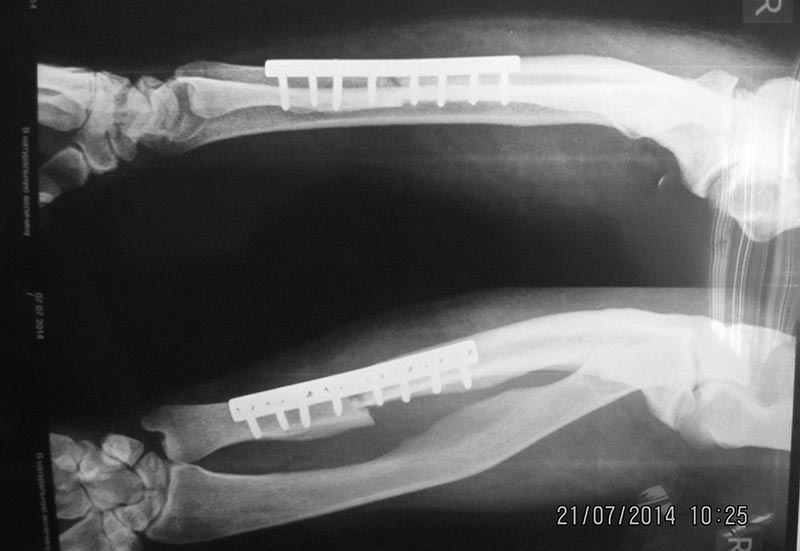

Выкладываю, как и обещал. За репозицию педплечья не осуждайте!

А действительно это Блаунт? Может быть ахондроплазик или дисхондроплазик. 2 недели назад оперировал, поставил обычную компрессионную пластину АО и никакой резекции. И у моего пациента выглядел как псевдартроз. Еще раз порасспрашивайте б-го, может удлиняли бедро? Не забыть бы в понедельник рентгены сфоткать и отправить Вам